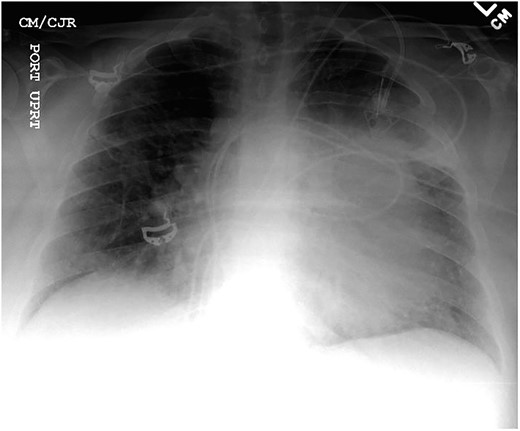

Cardiothoracic surgery team was consulted, and the patient underwent a pericardial window with 750 cc of serosanguinous fluid drained from her pericardial space. A chest tube placed status-post pericardial window, which initially continued to drain 500 cc of serosanguinous fluid, with fluid volume decreasing in the following 5 days with stable vital signs. The patient tolerated the switch to p.o. amiodarone and discharged upon her request to restart chemotherapy, after removal of her chest tube. Histopathology results of the pericardial fluid were positive for reactive mesothelial cells and chronic inflammation. Follow-up positron emission tomography (PET)/CT scan depicted increased uptake in the cardiac chamber (Fig. 4). Repeated echocardiography 2 months later depicted a return in pericardial fluid with the patient remaining hemodynamically stable with preserved ejection fraction.